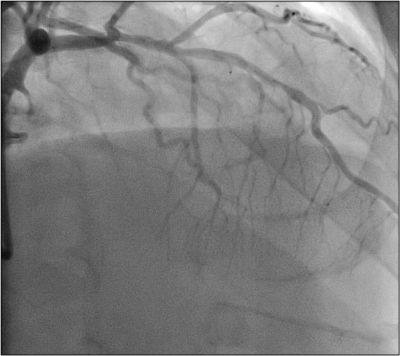

V dalším průběhu bylo přistupeno k rekanalizaci retrográdní cestou s využitím kolaterálního řečiště z RIA k periferii povodí ACD. Zaváděcí cévkou v ústí levé věnčité tepny byl po vodiči Balance Middle Weight (Abbott Vascular, USA) do úseku střední RIA zaveden mikrokatétr Corsair 150 cm (Asahi Intecc, Japonsko). Vodič byl vyměněn za hydrofilní rekanalizační vodič Sion Black a spolu s mikrokatétrem bylo proniknuto přes septální větev (obr. 6 a video 6)

a z ní vycházející kolaterálu do povodí distální části pravé věnčité tepny. Postupnou manipulací bylo proniknuto i retrográdně přes uzávěr až do proximální části pravé věnčité tepny a distální části zaváděcí cévky v jejím ústí. Následně po extrakci rekanalizačního vodiče mohl být skrz lumen ponechaného mikrokatétru retrográdně zaveden vodič RG3 300 cm (Asahi Intecc, Japonsko) s externalizací jeho měkkého konce zaváděcím katétrem v pravé věnčité tepně (obr. 7, 8 a video 7, 8).

Ostatní kroky výkonu již byly dále provedeny prográdní cestou – vodič RG3 ponechán in situ, mikrokatétr Corsair byl extrahován a opětovně zaveden po měkkém konci vodiče RG3 prográdně přes uzávěr tepny. Následně byl vodič RG3 vytažen a přes lumen mikrokatétru byl zaveden vodič Balance Middle Weight (Abbott Vascular, USA), po kterém byla provedena standardní postupná dilatace léze (obr. 9 a video 9)

balonkovými katétry Sprinter Legend 1,5 × 12 mm (Medtronic, USA) a Xperience 2,5 × 20 mm (iVascular, Španělsko). Po predilatacích chronického uzávěru a obnovení volného prográdního plnění tepny byl verifikován rozsah aterosklerotického postižení (obr. 10 a video 10),

léze byly následně ošetřeny konsekutivní implantací lékových stentů Synergy (Boston Scientific, USA) 3,0 × 38 mm a 3,5 × 16 mm s finální vysokotlakou postdilatací stentů tlakem 18 atm (obr. 11 a video 11).